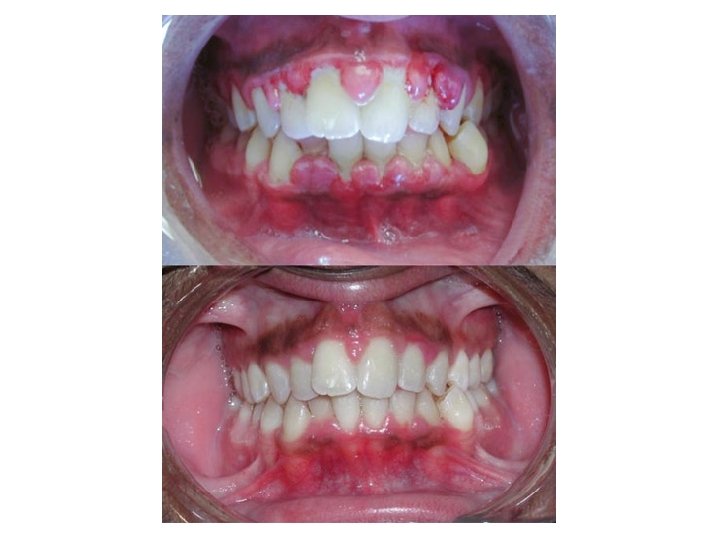

• GINGIVITIS: • es una enfermedad bucal generalmente bacteriana que provoca inflamación y sangrado de las encías, causada por los restos alimenticios quedan atrapados entre los dientes. Es muy frecuente que su origen sea causado por el crecimiento de las muelas del juicio, que produce una concavidad, que es donde se deposita el agente patógeno o bacteria. Esta enfermedad se puede desarrollar después de tres días de no realizar la higiene oral (cepillado de dientes y lengua). Cuando esta enfermedad evoluciona a un estado crónico, provoca bolsas periodontales, movilidad dentaria, sangrado excesivo y espontáneo, y pérdida del hueso alveolar que sostiene a los dientes, con la gran posibilidad de perder piezas dentales.